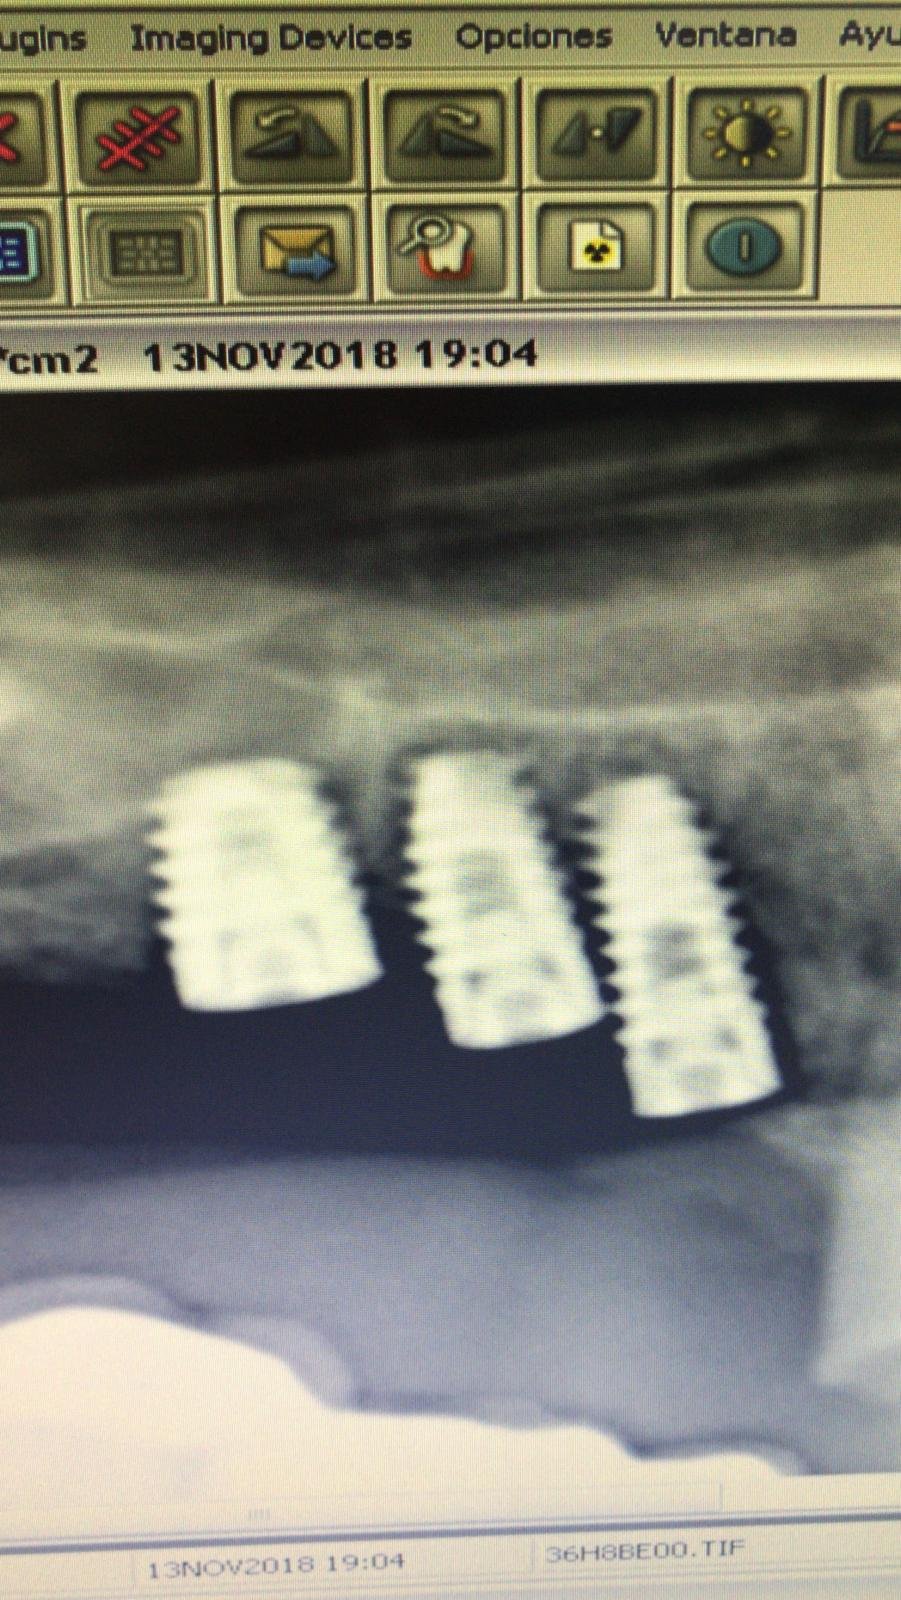

Caso de implante desconocido

Paciente que acude con periimplantitis en un puente cementado sobre 3 implantes que desconocemos, en posiciones 3.5, 3.6, 3.7. Decidimos mantener como corona unitaria el implante del 3.7. El pilar [...]